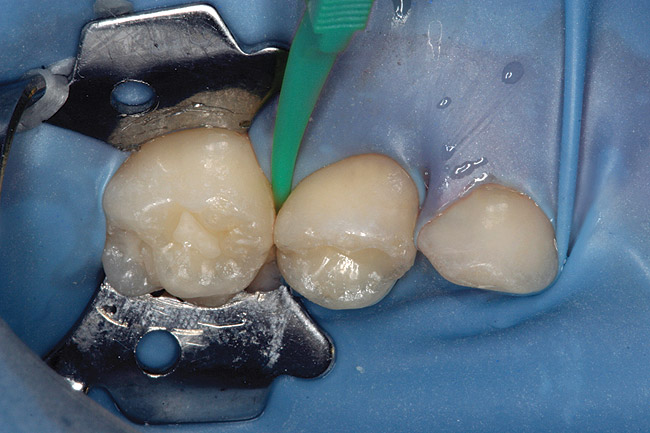

Caries infiltration is a simple, straightforward technique. Before treatment, the tooth should be thoroughly cleaned and isolated with a rubber dam (Figure 5 and Figure 6). Treatment kits contain all of the materials required for the technique (except the rubber dam), including specially designed proximal tips that are used for accurate delivery of the acid etch and infiltrant resin during the procedure. These carriers consist of an ultrathin film perforated on one side for direct placement at the treatment site, which protects adjacent teeth. The tips swivel 360°, allowing application from different angles. All syringes contained in the kit are screw-type applicators, which ensure controlled extrusion of the materials.

Figure 5  Preoperative photograph of tooth A.

Figure 5

Figure 6  Rubber dam and wedge in place.

Figure 6